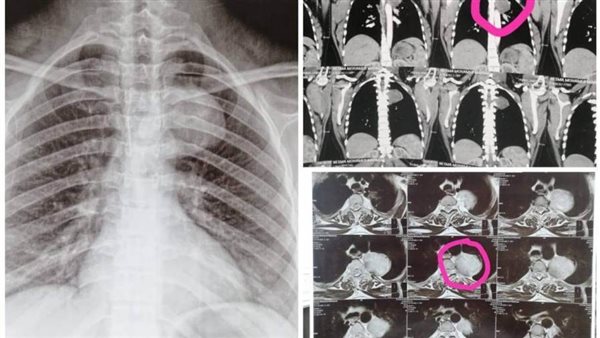

كان مستشفى الأمراض العصبية والنفسية وجراحة المخ والأعصاب برئاسة الأستاذ الدكتور طارق راجح، وقد استقبل سيدة تبلغ من العمر ٢٥ عاما، حامل في شهرها الأول، وتعاني من التهابات رئوية متكررة، وبعد فحصها من قبل فريق من المتخصصين بقسم الأمراض الصدرية، تحت إشراف الأستاذة الدكتورة صفاء وافي، والأطباء صفاء عبد الجيد، استشاري الأمراض الصدرية، والطبيب يوسف ثروت، طبيب مقيم بالقسم، بمشاركة الطبيبة شروق كيلاني، مدرس مساعد بقسم طب القلب، أظهرت الأشعات وجود ورم معقد بالعمود الفقري ممتد إلى الرئة.

ونظراً لخطورة الحالة، تم على الفور تشكيل لجنة علمية ضمت نخبة من الاستشاريين، وأقرت اللجنة بالإجماع ضرورة إجراء عملية جراحية عاجلة لاستئصال الورم.